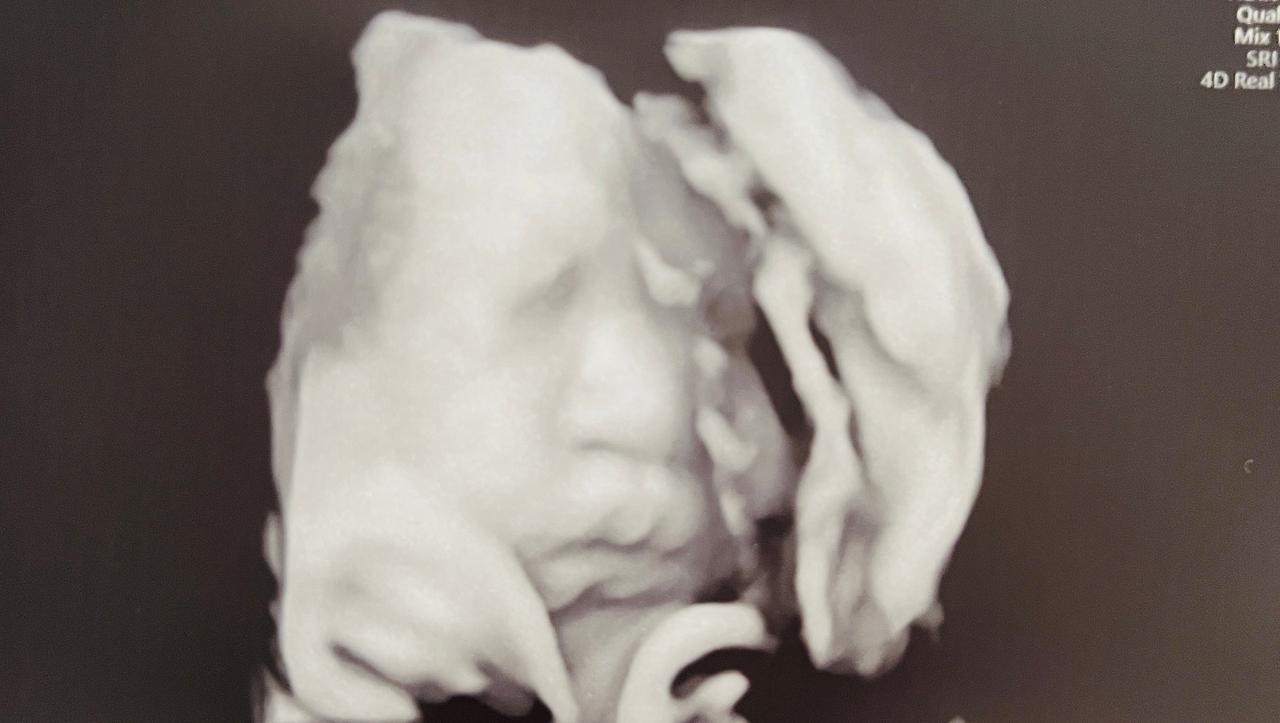

-패키지에 가입해도 4D 입체 초음파는 100만 동 추가 결제를 해야 한다.

(31주~34주 한 번은 패키지에 포함되어있음)

35주에 들어선 딸기, 건강하게 엄마 아빠랑 한 달 뒤에 만나자